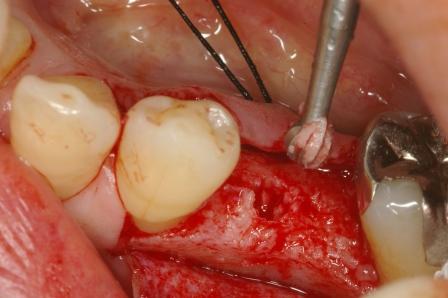

インプラント(人工の歯根)を入れた症例です。

歯の根っこにひびが入り、抜歯となった左下にインプラント(人工の歯根)を使って歯を入れました

前後の歯を削らずにすみます